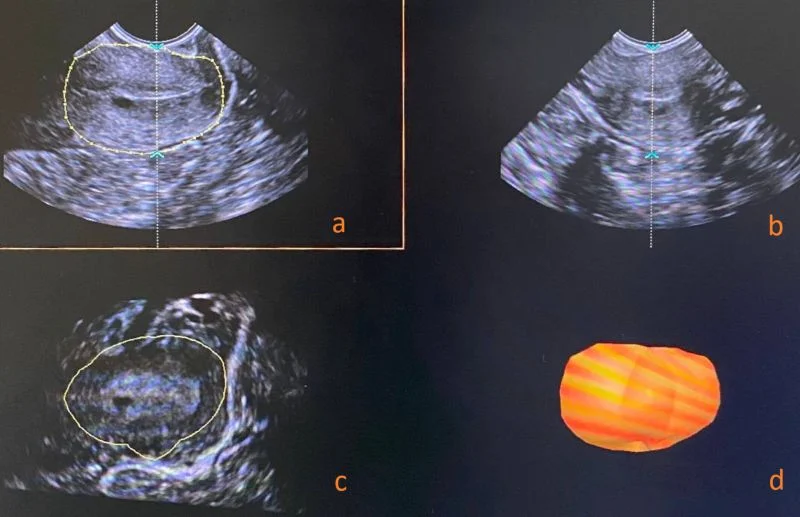

“‘Impact of large-loop excision of the transformation zone on cervical morphology: A prospective observational study’ – Flávia Zero Soares et al.

Title: Impact of large-loop excision of the transformation zone on cervical morphology: A prospective observational study

Authors: Flávia Zero Soares, Helmer Herren, Patrícia Pereira dos Santos Melli, Marília Veccechi Bijos Zaccaro, Silvana Maria Quintana